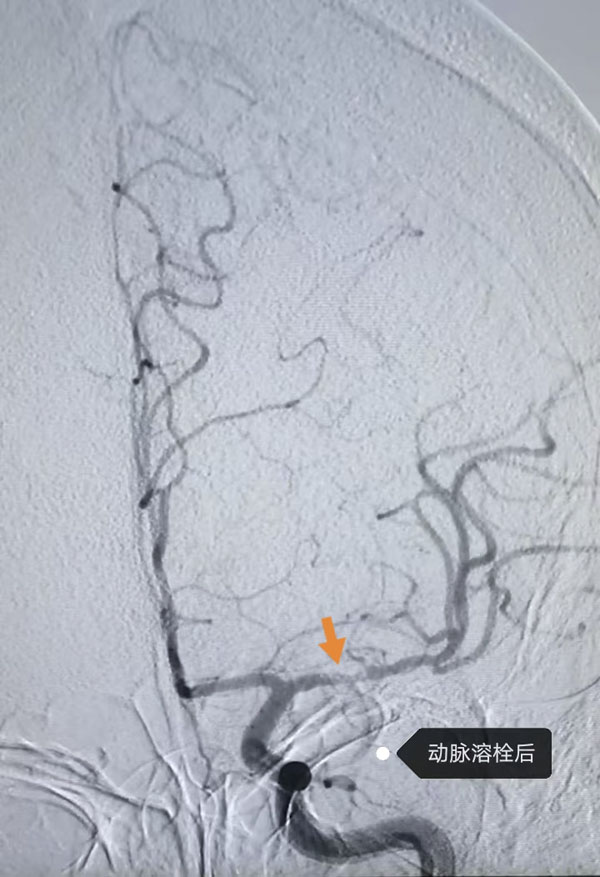

鉴于患者病情危急,接诊医生李晨曦紧急联系介入组李彦青医生启动卒中救治流程,在介入手术室的人员的帮助下,为其实施脑动脉造影术。术中,李彦青发现患者此次发病的责任血管“左侧大脑中动脉”虽存在血流再通,但局部仍为重度狭窄且血栓负荷重,遂决定通过左侧颈内动脉给药以改善局部血供。给药后,复查造影显示狭窄程度明显改善。术后,患者NIHSS评分(神经功能缺损评分)由入院时的8分快速降至3分,言语及右侧肢体活动不利明显改善。一周后出院时,评分进一步降至1分,言语及肢体活动基本恢复正常。